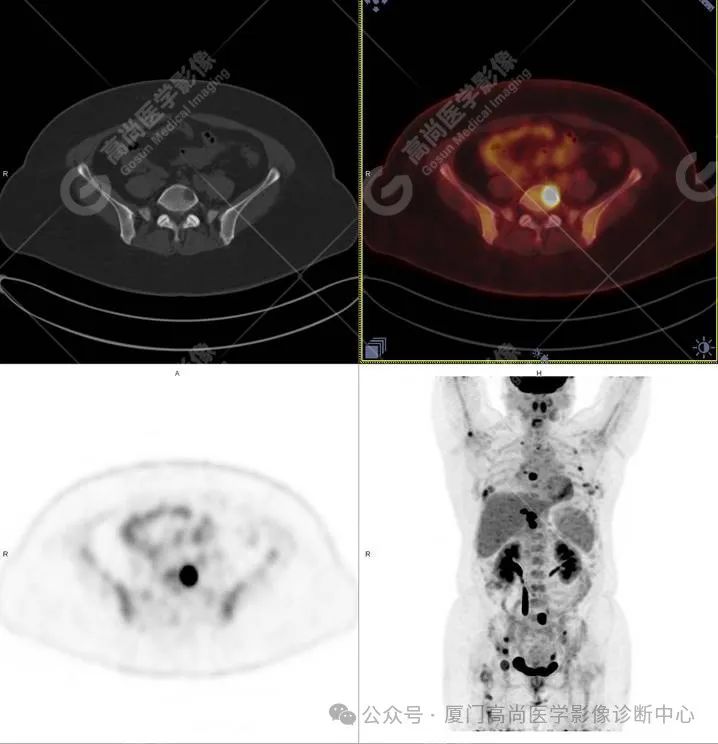

PET/CT 图像

PET/CT 检查所见: 胸 2、胸 5、胸 9、胸 10、腰 3、腰 5 椎体及其附件、双侧髂骨、右侧髋臼、右侧肱骨、右侧股骨上段、右侧第 2、6、7、9 肋及左侧第 2、4 肋多发溶骨性骨质破坏,病灶边缘欠光整,放射性摄取不同程度增高,SUVmax 3.7-17.7。

左侧乳腺外侧象限见小结节影,大小约 0.6×0.5 cm,放射性摄取增高,SUVmax 3.9,1 小时延迟显像放射性摄取进一步增高,SUVmax 4.1;左侧乳腺内侧象限皮肤局限性增厚,放射性摄取增高,SUVmax 4.5,1 小时延迟显像 SUVmax 4.7。

PET/CT 诊断: 考虑为左侧乳腺癌伴全身骨骼多发转移。

随访结果: 左侧乳腺神经内分泌癌。

关于 PET/CT 在原发性乳腺神经内分泌癌中的应用鲜有文献报道。本例患者因全身多发肿瘤骨转移,为查找原发病灶行 18F-FDG PET/CT 偶然发现罕见的乳腺神经内分泌癌。原发病灶仅有 0.6 cm 大小,若非选择 PET/CT 检查很难快速找到。文献报道应用 18F-FDG PET 显像对常规影像学检查不能找到原发灶的肿瘤患者寻找原发灶,约有 11.1%~63.2% 的患者能找到原发灶,结合 CT 准确定位并提供病灶解剖形态学信息后,PET/CT 寻找原发灶的准确性更高。此例充分体现了 PET/CT 高灵敏度、高分辨率、高速度和大视野优势。